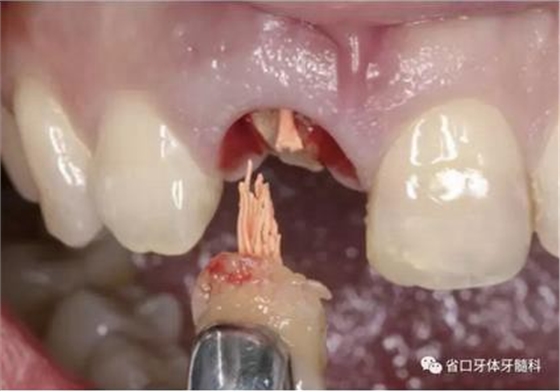

(1)微創(chuàng)拔牙及即刻種植:術(shù)前拍攝口內(nèi)照及實(shí)施牙周基礎(chǔ)治療。常 規(guī)消毒鋪巾阿替卡因局麻下微創(chuàng)拔除上頜右側(cè)中切牙,搔刮拔牙窩及根尖肉 芽組織。探測牙槽骨唇側(cè)骨壁及鄰面牙槽嵴完整,牙齦無撕裂。不翻瓣下于上頜右側(cè)中切牙缺隙近遠(yuǎn)中中點(diǎn)的腭側(cè)牙槽骨及根方定位,按照逐級預(yù)備的原則,緊貼牙槽窩腭側(cè)骨壁制備種植窩洞,植入Zimer®3.7mm×13mm TSV種植體1顆,植入扭矩>35N·cm,以O(shè)sstell測量種植體的ISQ值為68。 種植體平臺位于唇側(cè)齦緣中點(diǎn)下3mm,與唇側(cè)骨壁內(nèi)側(cè)面形成的跳躍間 隙約2mm,置入Bio-Oss®細(xì)顆粒骨粉0.25g,上愈合基臺關(guān)閉創(chuàng)口。術(shù)后 CBCT檢查顯示:種植體利用牙槽窩根方骨質(zhì)固位,緊貼牙槽窩腭側(cè)骨壁, 其唇側(cè)面與牙槽窩唇側(cè)骨壁的內(nèi)側(cè)面所形成的跳躍間隙(約2mm)可見顆 粒狀顯影物充填。牙槽窩的唇側(cè)骨壁及唇側(cè)倒凹無缺損穿孔。

圖5 微創(chuàng)拔牙

圖6 微創(chuàng)拔牙

圖7 根尖區(qū)肉芽

圖8 刮除肉芽組織